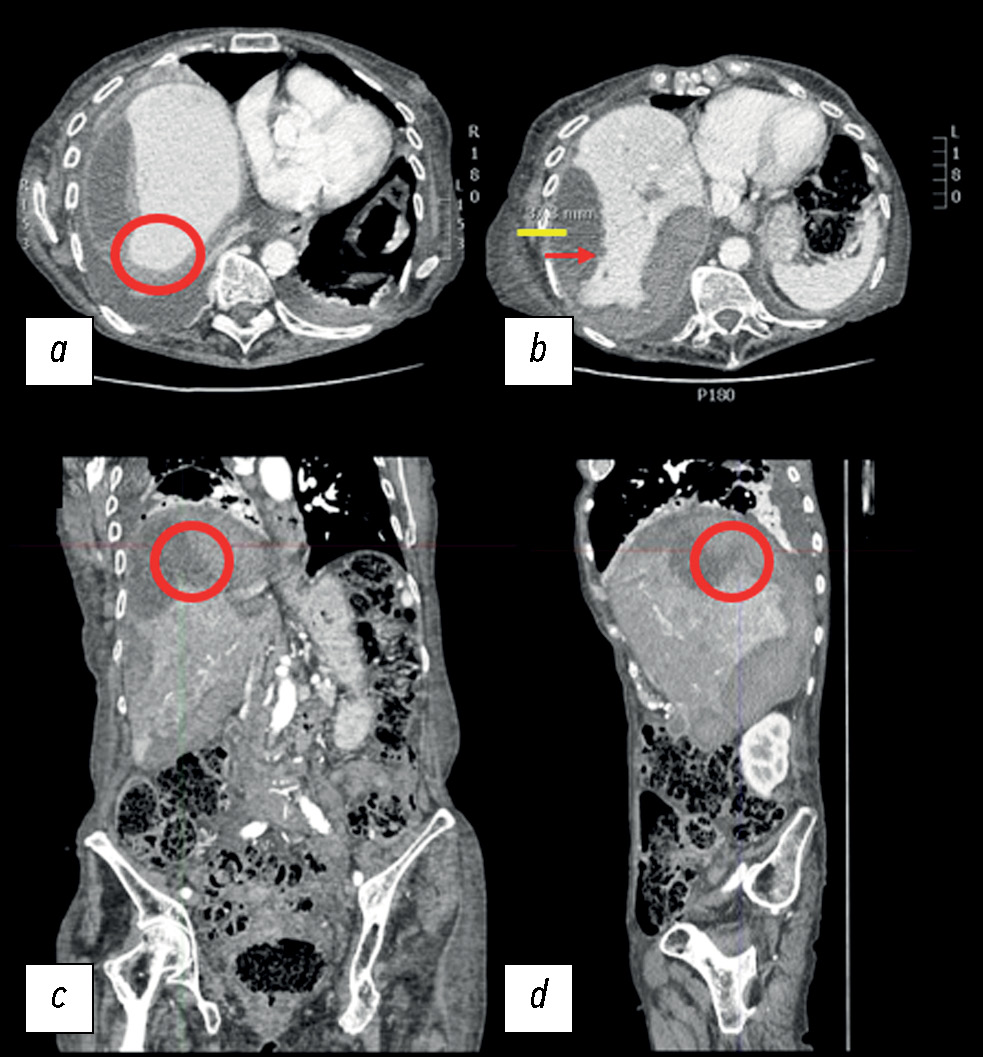

После лечения пациентка была госпитализирована более чем на 2 недели для надлежащего лечения и разрешения проявлений сопутствующих заболеваний. На контрольной КТ после ангиографии не выявили признаков активного кровотечения или осложнений выполненных вмешательств, таких как некроз печени, а выявленная ранее интракапсулярная печёночная гематома стабильно оставалась в стадии разрешения. Субкапсулярная гематома также по-прежнему визуализировалась, но была стабильной (рис. 5). Для разрешения состояния потребовалось более длительное пребывание в стационаре.

Рис. 5. Снимки компьютерной томографии с контрастным усилением в артериальной фазе через несколько дней после ангиографии: a, b — аксиальная плоскость; c — корональная плоскость; d — сагиттальная плоскость.

Компьютерную томографию с контрастным усилением в артериальной фазе провели через несколько дней после ангиографии. На контрольном снимке не было рентгенологических признаков, указывающих на активную экстравазацию контрастного вещества в VIII сегменте печени, поскольку в отмеченной красным кругом области в различных плоскостях: аксиальной, корональной и сагиттальной — не было отмечено гиперденсных пятен. Интракапсулярная гематома находилась в стадии разрешения: около 3,5 см, измерено на снимке b и выделено жёлтым цветом, по сравнению с 5 см на предыдущей компьютерной томографии (см. рис. 2).